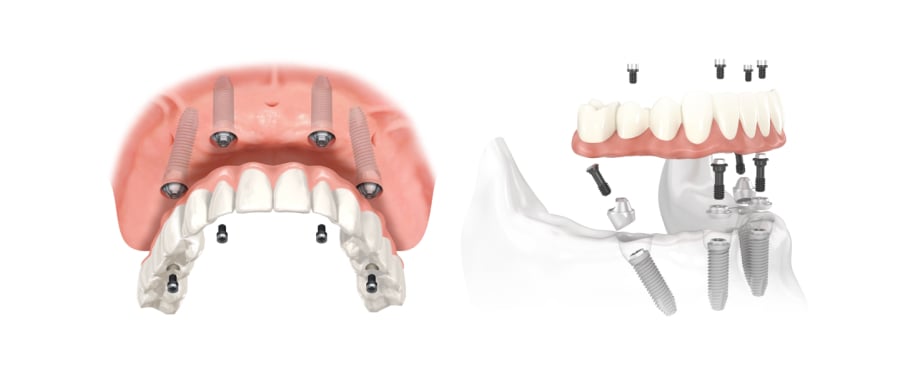

Пошаговое руководство по установке съёмного протеза на импланты